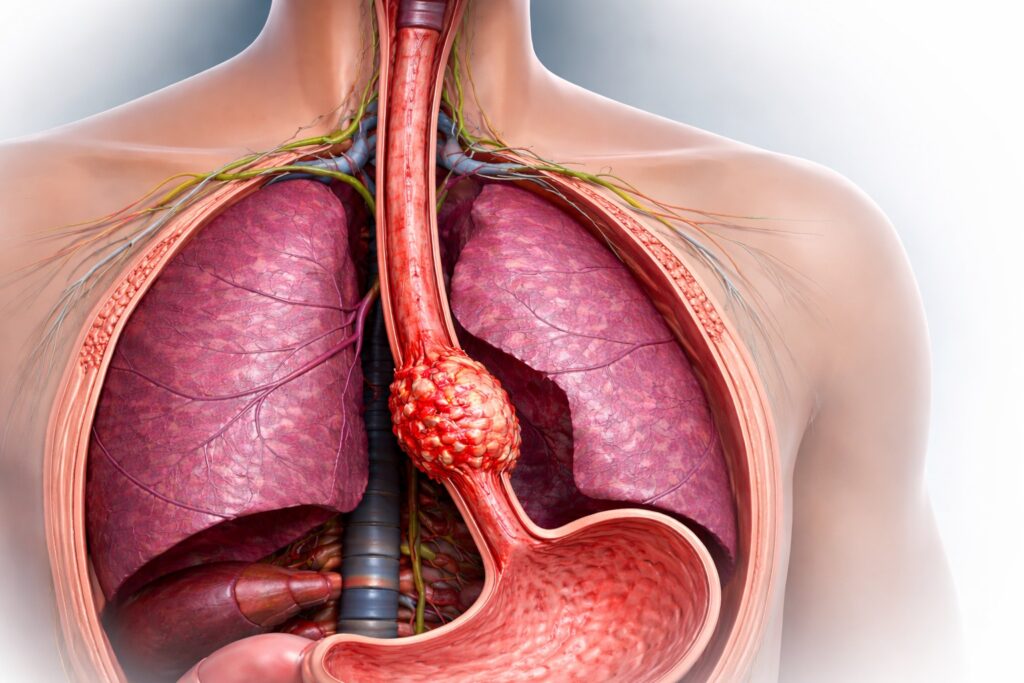

Understanding the Esophagus and Esophageal Cancer

The esophagus is a hollow, muscular organ approximately 25 cm long that connects the throat (pharynx) to the stomach. Its primary function is to transport food through coordinated muscular contractions known as peristalsis.

Esophageal cancer develops when abnormal cells in the lining of the esophagus begin to grow uncontrollably. Over time, these cells can invade deeper layers of the esophageal wall and spread to nearby lymph nodes or distant organs.

- Early and Advanced Symptoms of Esophageal Cancer

- One of the major challenges with esophageal cancer is that early symptoms are often mild or overlooked.

Early Symptoms

- Difficulty swallowing (dysphagia), initially with solid foods

- Sensation of food getting stuck in the chest

- Mild chest discomfort or heartburn

- Unintentional weight loss

- Loss of appetite

- Advanced Symptoms

- Progressive difficulty swallowing liquids

- Persistent chest pain or pressure

- Hoarseness of voice

- Chronic cough or choking episodes

- Vomiting blood or black stools

- Severe weight loss and fatigue

- Any persistent swallowing difficulty or unexplained weight loss should prompt immediate medical evaluation.